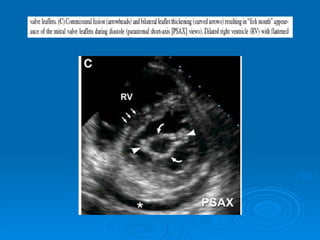

Echo-doppler Cardiaque Echographie bidimentionnelle: Épaississement de la valve Diminution d’ouverture valvulaire Aspect caractéristique en genou fléchi de la GVM Mesure de la surface mitrale Recherche de calcifications Recherche de thrombis intra auriculaire gauche Dilatation de OG Etude de l’appareil sous valvulaire

Echo-doppler Cardiaque Echographiebidimentionnelle: Épaississement de la valve Diminution d’ouverture valvulaire Aspect caractéristique en genou fléchi de la GVM Mesure de la surface mitrale Recherche de calcifications Recherche de thrombis intra auriculaire gauche Dilatation de OG Etude de l’appareil sous valvulaire